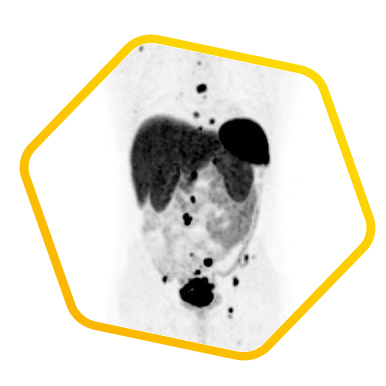

Neuroendocrine Tumor

Dual tracer PET/CT (F-18 FDG and Ga-68 DOTATATE) are used for the metastatic evaluation of neuroendocrine tumor.